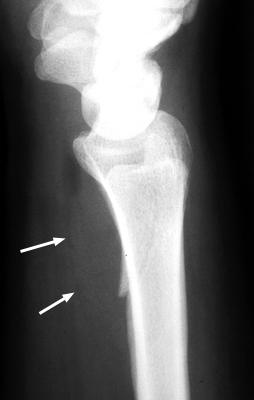

A. Normal pronator fat pad. B. Displaced pronator fat pad. Lateral wrist x-ray, a reveals abnormal bulging of a fat plane adjacent to an area of underlying osseous injury. The ventral bulging of the fat plane overlying the pronator quadratus muscle has been coined the "pronator sign." Although it typically means underlying fracture is present, it may also be seen in simple soft-tissue injury of the same region. It is a good sign and should alert the radiologist of possible fracture when present.

Normal fat pad - Click on the image for a larger versionALateral Wrist - Click on the image for a larger versionB